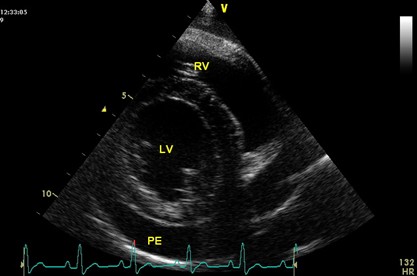

• Pathophysiology of PE

• Causes and prognosis of different types of PE

• Diagnosis

• Management, including draining and surgical options